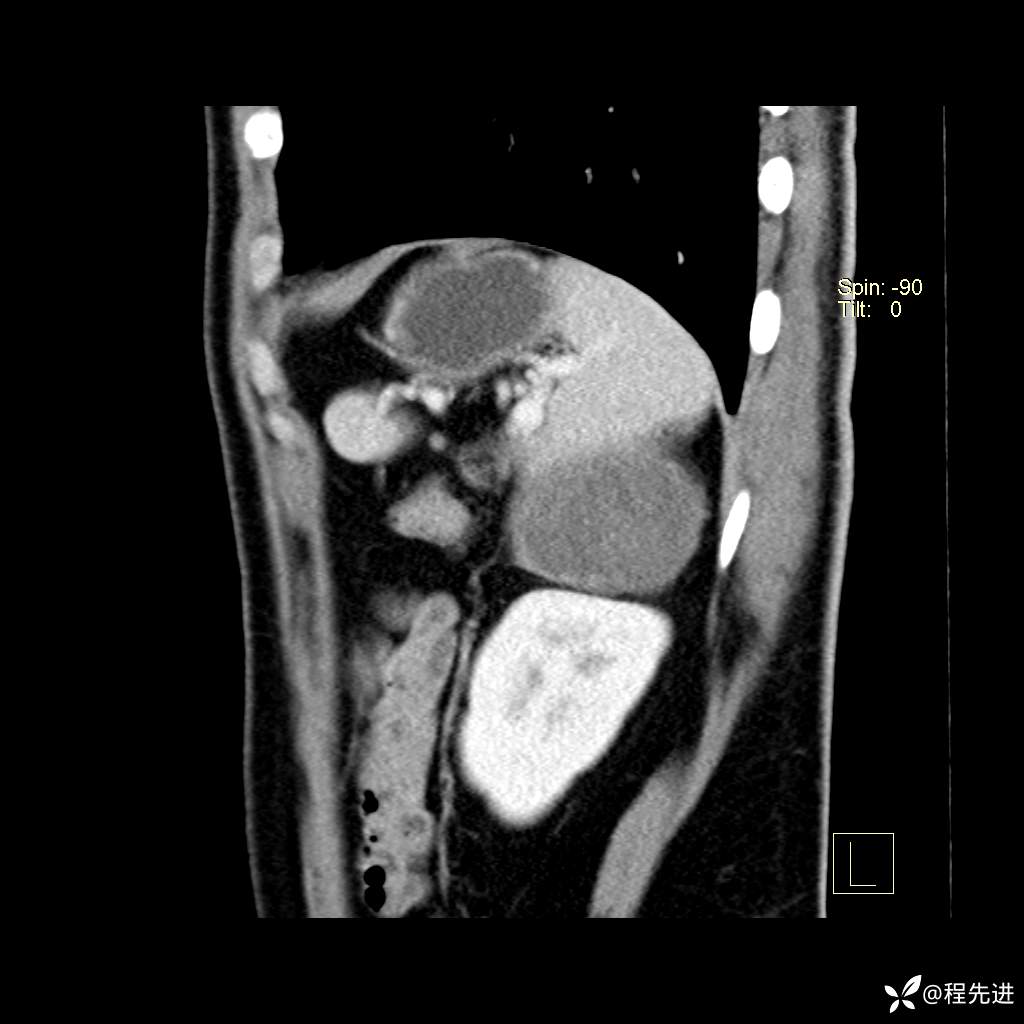

矢状位重建: